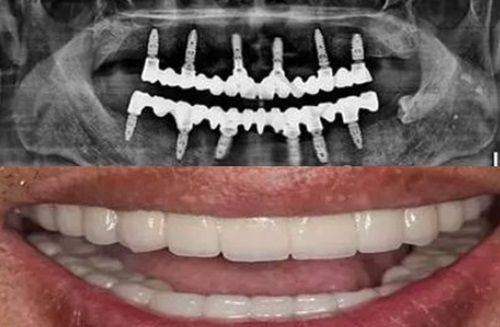

在激烈的市场竞争下,2024年西安各口腔医院收费标准有一定下调。种植牙方面,价格基本在2980 - 8800元起一颗。其中,国产种植牙价格在2680 - 3980元起一颗(创英、威高);韩国进口种植牙价格在2980 - 4980元起一颗(登腾、奥齿泰、美格真、仕诺康);美国进口种植牙价格在4980 - 6980元起一颗(皓圣、杰美);德国进口种植牙价格在5980元起一颗(icx、朗斯、camlog、贝格);瑞士进口种植牙价格在6980 - 10800元起一颗(iti、sic);瑞典进口种植牙在7980 - 10800元起一颗(诺贝尔、astra)。